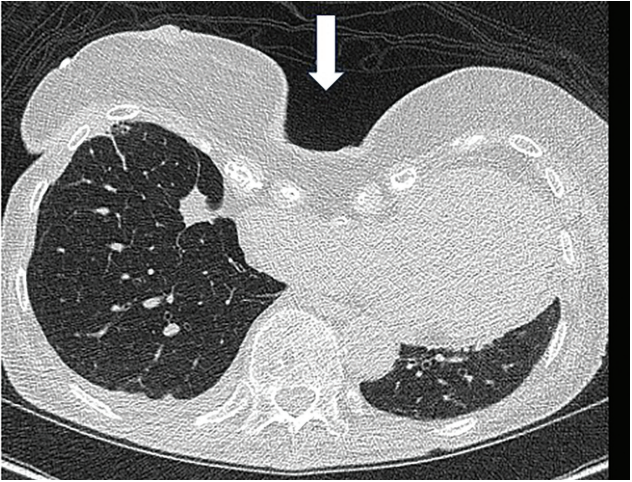

Kern-Fig1-CLD-MarchApril 2026_0.png

Figure 1. Computed tomography angiography (CTA) of chest showing indentation of sternum defining the pectus excavatum (arrow).